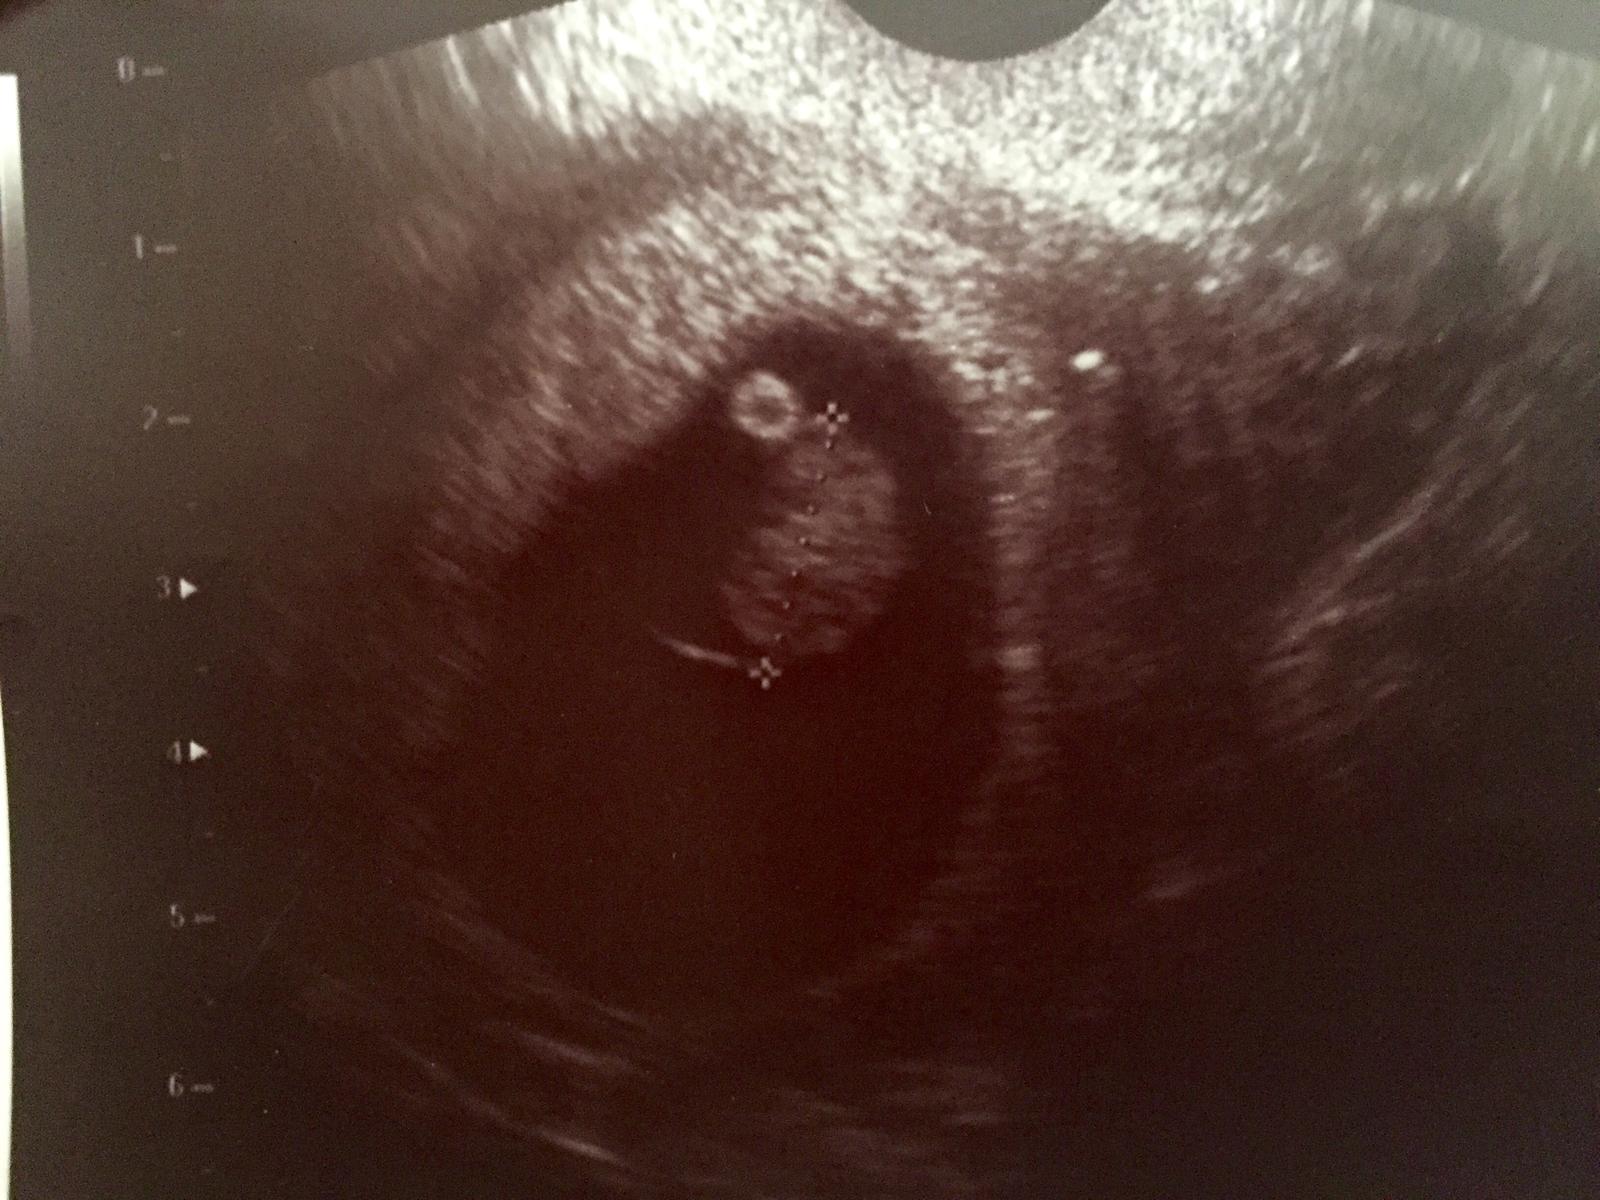

Doktor sa smial,ze ma svatoziaru, ale inak je to zlty vacok